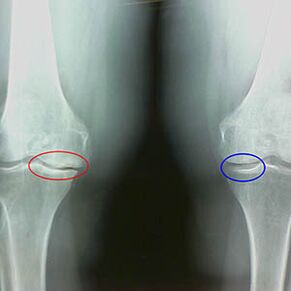

Artrosi maila zehaztea x -Ray-k gertatzen dahezur egituren prozesu patologikoan parte hartzea agerian uztea. Haien aldaketak adierazten du muskulu-sistema 5-10 urte daramala desoreka izan dela. Orokorrean, jendea Hainbat urtez minak minak izaten dituzte.

Artrosiaren lehen etapanIstripuz hautematen dena, hezur-spurs gehikuntza txiki bat gertatzen da. Hazkundeak artikulazioaren ezegonkortasun handieneko lekuetan agertzen dira. Normalean, gaixoek oso gutxitan izaten dute mina edo ondoeza mugimenduan zehar.

Artrosiaren bigarren etapa erraza da. Erradiografiak hezur-isuri garrantzitsuak erakusten ditu, baina kartilagoak ez du eraginik. Likido sinovialen zenbatekoa murriztu egiten da, baina minaren sintomak ibilaldi luzeak eta korrika egin ondoren, kolpeak eta minak okertu eta belaunetan kokatzen direnean.

X-X-Belauneko Artrosiaren bigarren etapa ezaugarriak:

- Tibiako tuberkuluen arteko tuberkuluen punta-puntuak, gurutze-ligamentua erantsita dagoenean;

- alde medialaren gainean dagoen hutsunea murriztea;

- Hezurren kondoluen ertz seinaleak alboetako alboetan, gero eta gutxiagotan, Valgus edo Variior Baterako deformazioaren garapenaren arabera.

Larsen bigarren etaparako % 50 baino gehiagoko hutsunea murriztea ezaugarria da, baina hori dinamikan edo konparazioan soilik egiaztatu daiteke ez bezala.

Erradiografiak osteofitoen presentzia erakusten du, femoralen eta tibiako hezurren arteko espazioaren aldaketa, eta horrek kartilagoaren galera adierazten du belaunean. Batzuetan, belauneko artikulazioen X -Ray kartilagoen higaduraren seinale garrantzitsuak erakusten dira, baina gaixoek ez dute minik izaten.Aitzitik, lehen etaparen artrosiak belaunaren funtzioa eten dezake, minaren kausa gihar hipotonikoak baitira.